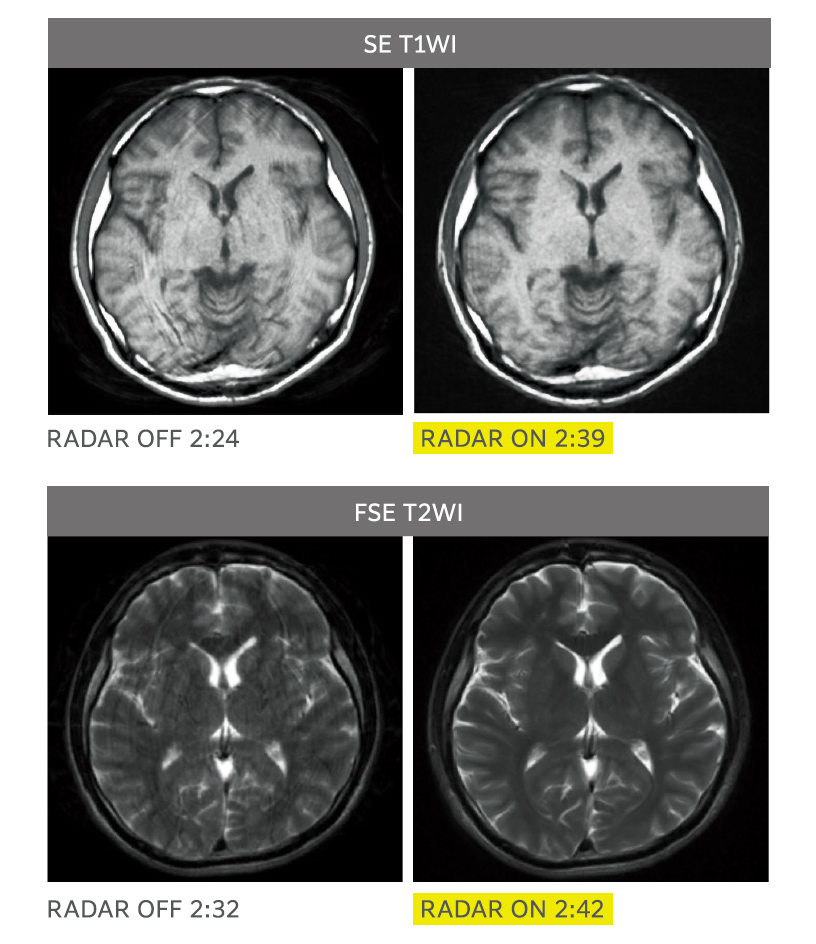

RADAR mitigates motion artifacts enhancing ease of use when imaging with many sequences, all receiver coils, and arbitrary cross-sections. RADAR can be used in combination with highspeed imaging. ECHELON Smart supports TOF and GrE sequences and is compatible with the combined use of RADAR for most of the sequences required for routine head examinations, thus realizing "All Around RADAR."

RADAR has been applied to GrE sequences using a high-precision signal correction technology. This has enabled the combined use of RADAR in all sequences required for routine head examinations.